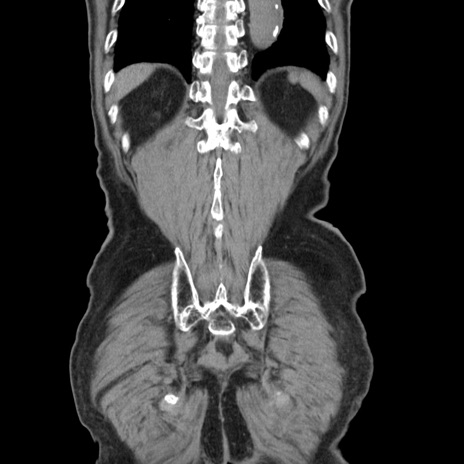

症例24(冠状断像)

【症例】80歳代男性

【主訴】左側腹部痛、嘔吐

【現病歴】本日早朝より左腹部に痛みあり。昼頃嘔吐認めたため、救急要請。

【既往歴】直腸癌(Mile手術)、胆摘

【身体所見】意識清明、BT 35.9℃、BP 221/93mmHg、SpO2 97%(RA) 、腹部:左ストーマ周囲に限局性の腹部膨隆あり。 膨隆部自発痛・圧痛あり・軟。

【データ】WBC 7700、CRP 0.09